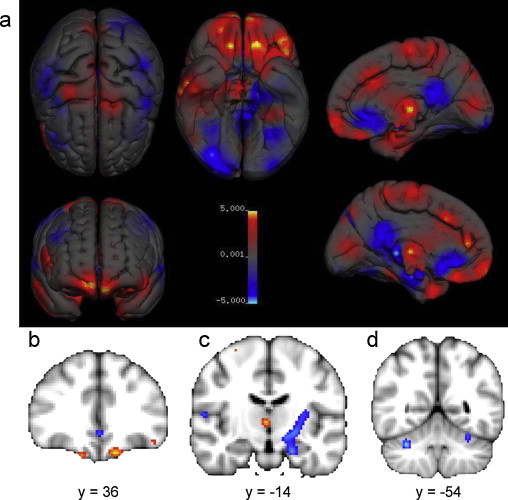

在灰质差异上,男女的体积和密度同样各有侧重。

灰质体积差异:

女性>男性为红色,男性>女性为蓝色

整体来看,男性的边缘系统灰质具有更大的体积和密度,女性的语言系统相关灰质具有更大的体积和密度。